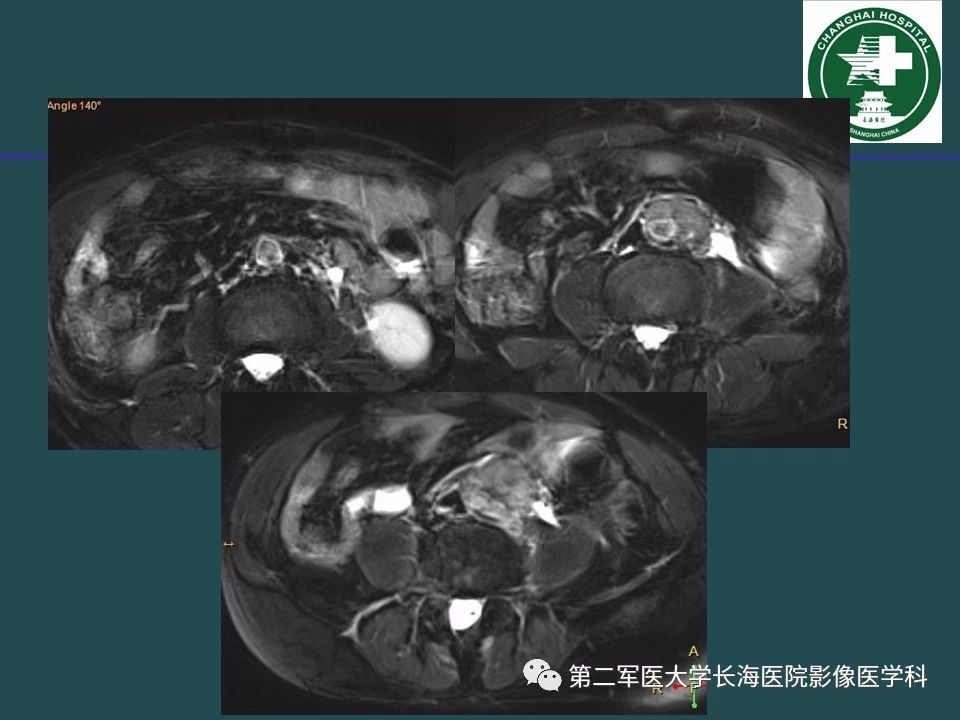

常见的腹膜后占位诊断及鉴别诊断

来源:第二军医大学长海医院影像医学科